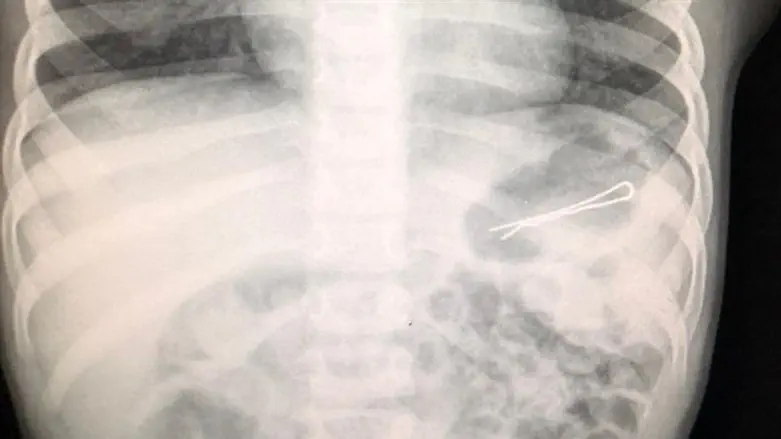

חייו של פעוט בן שלוש ניצלו השבוע לאחר שהובא למרכז הרפואי זיו כשבבטנו נמצאה סיכת ראש באורך 6 ס"מ אותה בלע.

בעקבות קושי בנשימה בוצע צילום רנטגן ובו נראתה בבירור הסיכה שהחלה לעבור בשער הקיבה ולכן היה צורך בביצוע גסטרוסקופיה, תוך החדרת צינור מהגרון לקשת התריסריון ושליפת הסיכה בזהירות רבה, כיוון שאחד מצדדיה חד.

ד"ר הינו אמר כי "ילדים בולעים גופים זרים שונים, אבל יש כמה שדורשים התייחסות מיוחדת והוצאה אנדוסקופית מיידית כשהם בטווח השגה, כמו סוללות וכפתור בושט. במקרה הזה, הפעוט בן ה-3 בלע סיכת ראש באורך 6 ס"מ שנתקעה בקשת התריסריון ולכן נדרשה הוצאה אנדוסקופית בהרדמה כללית בחדר. לאחר שהילד התאושש וחש בטוב, הוא שוחרר לביתו".